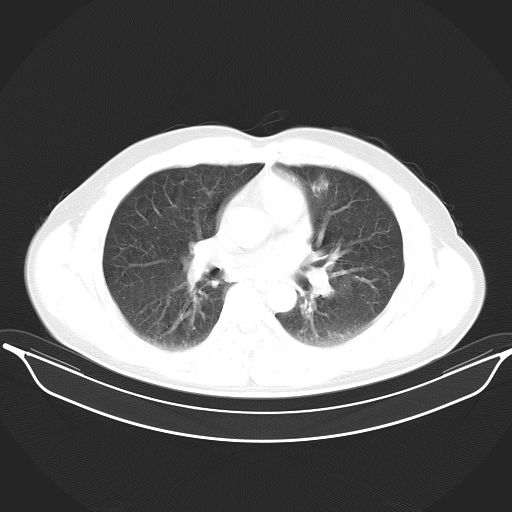

标题: CT25490:男,40岁,体检发现;无其它不适。 [打印本页]

标题: CT25490:男,40岁,体检发现;无其它不适。

倾向于结核

多考虑结核。

考虑结核

考虑肺霉菌病。

转移性肺肿瘤不排除,建议结合相关检查考虑

考虑右下肺周围性肺癌并肺内多发转移,纵隔淋巴结转移!

考虑肺癌并肺内转移可能性大。

考虑过敏性肺炎,建议抗炎后复查,转移瘤及tb待排

支持 !考虑右下肺周围性肺癌并肺内多发转移,纵隔淋巴结转移,(气管前腔静脉后,隆突下,主动脉弓下都有了)

1、均为转移,原发灶不在肺内。2、肺癌肺转移。

感染性肉芽肿